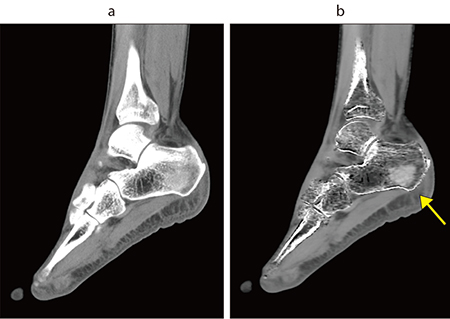

図1 踵骨 Dual Energy撮影

a:骨条件 b:VNCa

VNCa画像では骨折(↑)が確認できる。

同院では、整形外科領域の骨折、特にX線や単純CTでは判断が難しい不顕性骨折に対して、Dual Energy CT(DECT)を用いたVirtual Non Calcium(VNCa)画像での描出を行っている。同院では、増加する高齢者の骨折に対応するため、2024年に「高齢者骨折センター」を開設、手術からリハビリまで迅速かつ的確に診療を提供する体制を整えた。センター長を務める伊藤副院長はDECTについて、「X線や単純CTでは判断が難しい骨折でも、DECTのVNCa画像で明確に描出されるケースがあります。変性との違いを確認するためMRIは撮像しますが、CTでわかることで、より迅速な診断と治療方針の決定が可能です」と述べる。DECTは明らかな骨折を除いて骨折疑いの症例で撮影しており、椎体骨折や大腿骨近位部骨折、踵骨骨折、手根骨骨折などで有用だとのことだ。整形外科領域のDECTについては牧野医師も、「DECTで骨髄浮腫が明瞭に描出できるようになって、圧迫骨折や大腿骨頭の頸部骨折、緊急の腰椎ヘルニアなどの診断に有用です」と評価する。

DECT撮影は前機種の時から行っていたが酒井技師は、「Aquilion Serveでは、AiCE-iと非剛体位置合わせによって1回の撮影で診断が可能な画像を得ることができるようになり、安心して検査ができるようになりました」と述べる。また、酒井技師は、「VNCa画像は、救急の当直で整形外科の専門医以外が担当する場合に骨折がわかりやすく、入院などの的確な判断が可能です。休日や夜間は緊急でMRIを撮ることが難しいこともあり、CTで対応できるメリットは大きいですね」と述べる。DECTについては、今後、整形外科だけでなく口腔外科での骨折や出血の判定などにも展開していきたいと酒井技師は言う。